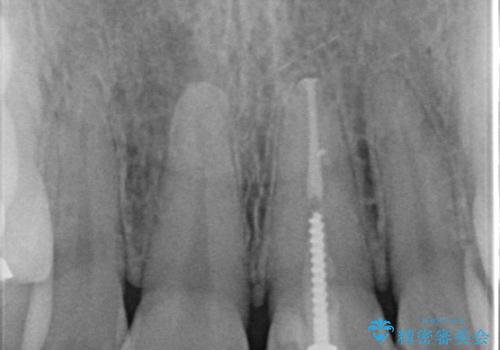

- 「前歯の色が気になる」を主訴に来院された患者様です。前歯が咬んでない開咬という状態のため、矯正治療を勧めましたが、患者様がご希望されなかったためオールセラミッククラウンで治療を行いました。右上1番は、神経の検査の結果、神経が死んでいたため根管療から行いました。左上1番は、金属の土台が入っていたのとラバーダムシートを使用せず根管治療が行われていたため、再度根管治療から行いました。その後ファイバーコアをたてオールセラミッククラウンで治療を行いました。

※右上1番の神経が死んでいた理由は定かではありませんが、保険治療で使用される材料では劣化により歯と材料の隙間が著しくなります。そこから細菌が侵入し神経が死んでしまう事があります。

※根管治療では根管内に細菌を入れない事がとても大切なので必ずラバーダムシートとマイクロスコープを使用して根管治療を行っています。